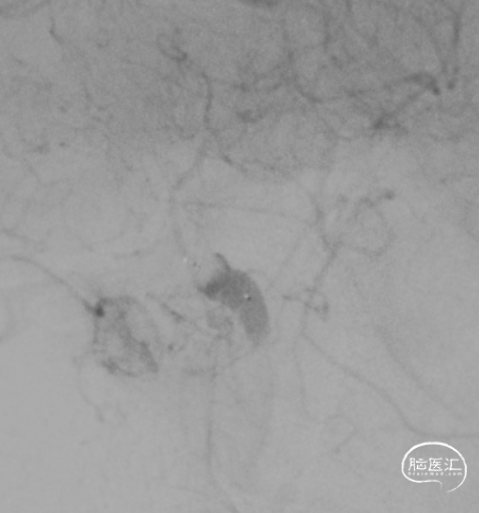

DSA

平均宽度(4.5+3.8)=4.2mm,最小深度7.5mm,选择SL5x3

微导管到位动脉瘤腔

通过VIA17释放web

造影可见造影剂滞留

手推造影-推挤-造影

解脱web

术后正侧位造影

术后CBCT